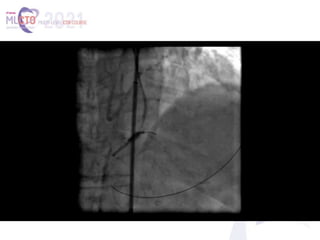

(A, B) Perforation caused by antegrade

ballooning. (C) Retrograde crossing of the lesion with

a guidewire away from the perforation site (true

retrograde crossing). (D) Sealing the perforation by

crushing the body of the lesion onto the vessel

walls. (E, F) An alternative scenario, where the

retrograde wire navigated the lesion through the

connection created by antegrade ballooning (reverse

controlled antegrade and retrograde subintimal

tracking technique). In this unfavorable scenario, a

covered stent would be necessary.